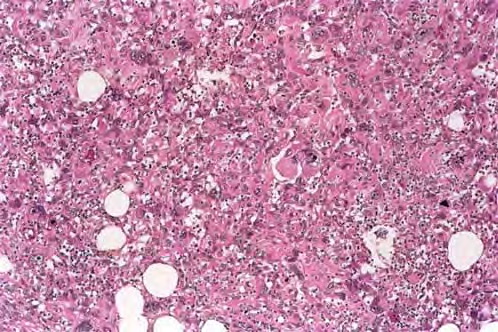

malignant-fibrous-histiocytoma